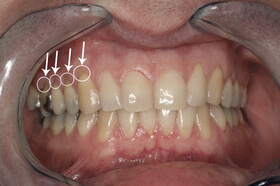

A fogágybetegség kezelése után a beteg fogszabályozó készüléket kap az esztétikai eltérés korrekciójára

A kezelés végén a fogszabályozó készülék eltávolítása előtt

A végeredmény, a frontfogak a belső oldalon összesínezve